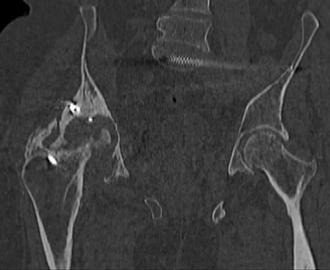

Пациент 49 лет, паровозная травма 23.2.2006, получил вертикальная

нестабильное повреждение таза, разрыв левого крестцово-подвздошного

сочленения, перелом лонной, седалищной костей слева, T-образный

оскольчатый перелом правой вертлужной впадины с переломом заднего

края, вывих правого бедра, посттравматическая пояснично-крестцовая

плексопатия с обеих сторон, паралич мышц правой голени.

В день травмы - вправление вывиха, скелетное вытяжение, 14.3.2006

чрескостный остеосинтез таза. 20.4.2006 остеосинтез правой вертлужной

впадины пластинами, осложнившийся нагноением межмышечной гематомы

правой ягодичной области. Получал консервативное лечение, было

достигнуто полное заживление раны. 24.7.2006 введены илиосакральные

винты слева. С декабря 2006 года и по настоящее время ходит на

костылях без опоры на правую ногу. Планируется THA. Помогите

определиться с вариантом костной пластики? И какую укрепляющую

конструкцию использовать?